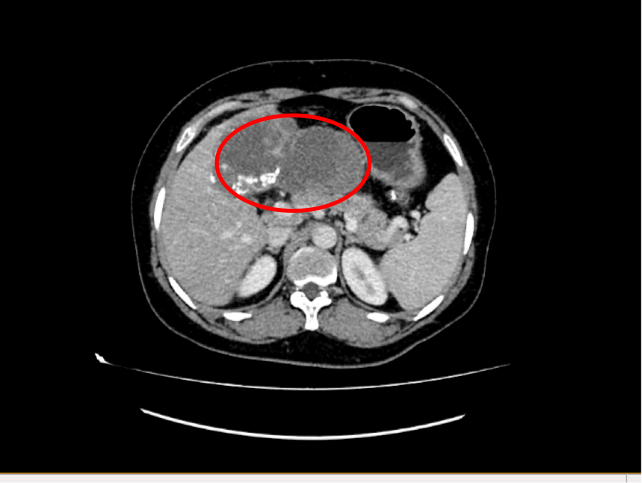

王女士入院后,检查结果令人忧心。她的肝脏占位病变,尤其是左肝肿瘤体积巨大,且与肝门及肝脏内大血管紧密相连,手术难度较大。面对挑战,潘耀振教授带领团队组织多学科专家会诊,认真研究了患者的病史,进行相关辅助检查,全面评估了患者病情,充分结合家属的顾虑因素,果断决定为王女士行肝癌切除+胆囊切除术的治疗方案。

近日,由潘耀振教授主刀,带领王兴副主任及团队实施了手术。腹腔探查见患者肿瘤位于左肝,呈突出性生长,巨大的包块令人触目惊心,与周围组织重度粘连,肿瘤压迫了胃、胰腺、结肠等重要脏器,但肿瘤医院的外科专家们凭借精湛的技术,术中精细操作、默契配合,成功完成了扩大左半肝及肿瘤的切除,取出的肿瘤尺寸达18x14cm,术中出血量极少,手术非常成功。

患者术前影像